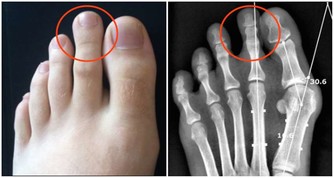

從中醫角度看,手腳冰涼很大程度上是由腎陽虛引起的,因為腎陽是我們全身陽氣的根本。如果腎陽充足,全身的臟腑、形體、關竅就能夠得到溫煦,各種生理活動都能夠正常運行。如果腎陽虛衰,那麼它對身體、四肢的溫煦作用就會隨之減弱,臟腑的功能也會減弱,機體的新陳代謝就會緩慢,產熱就會不足,當然就會出現手腳冰涼的症狀了。